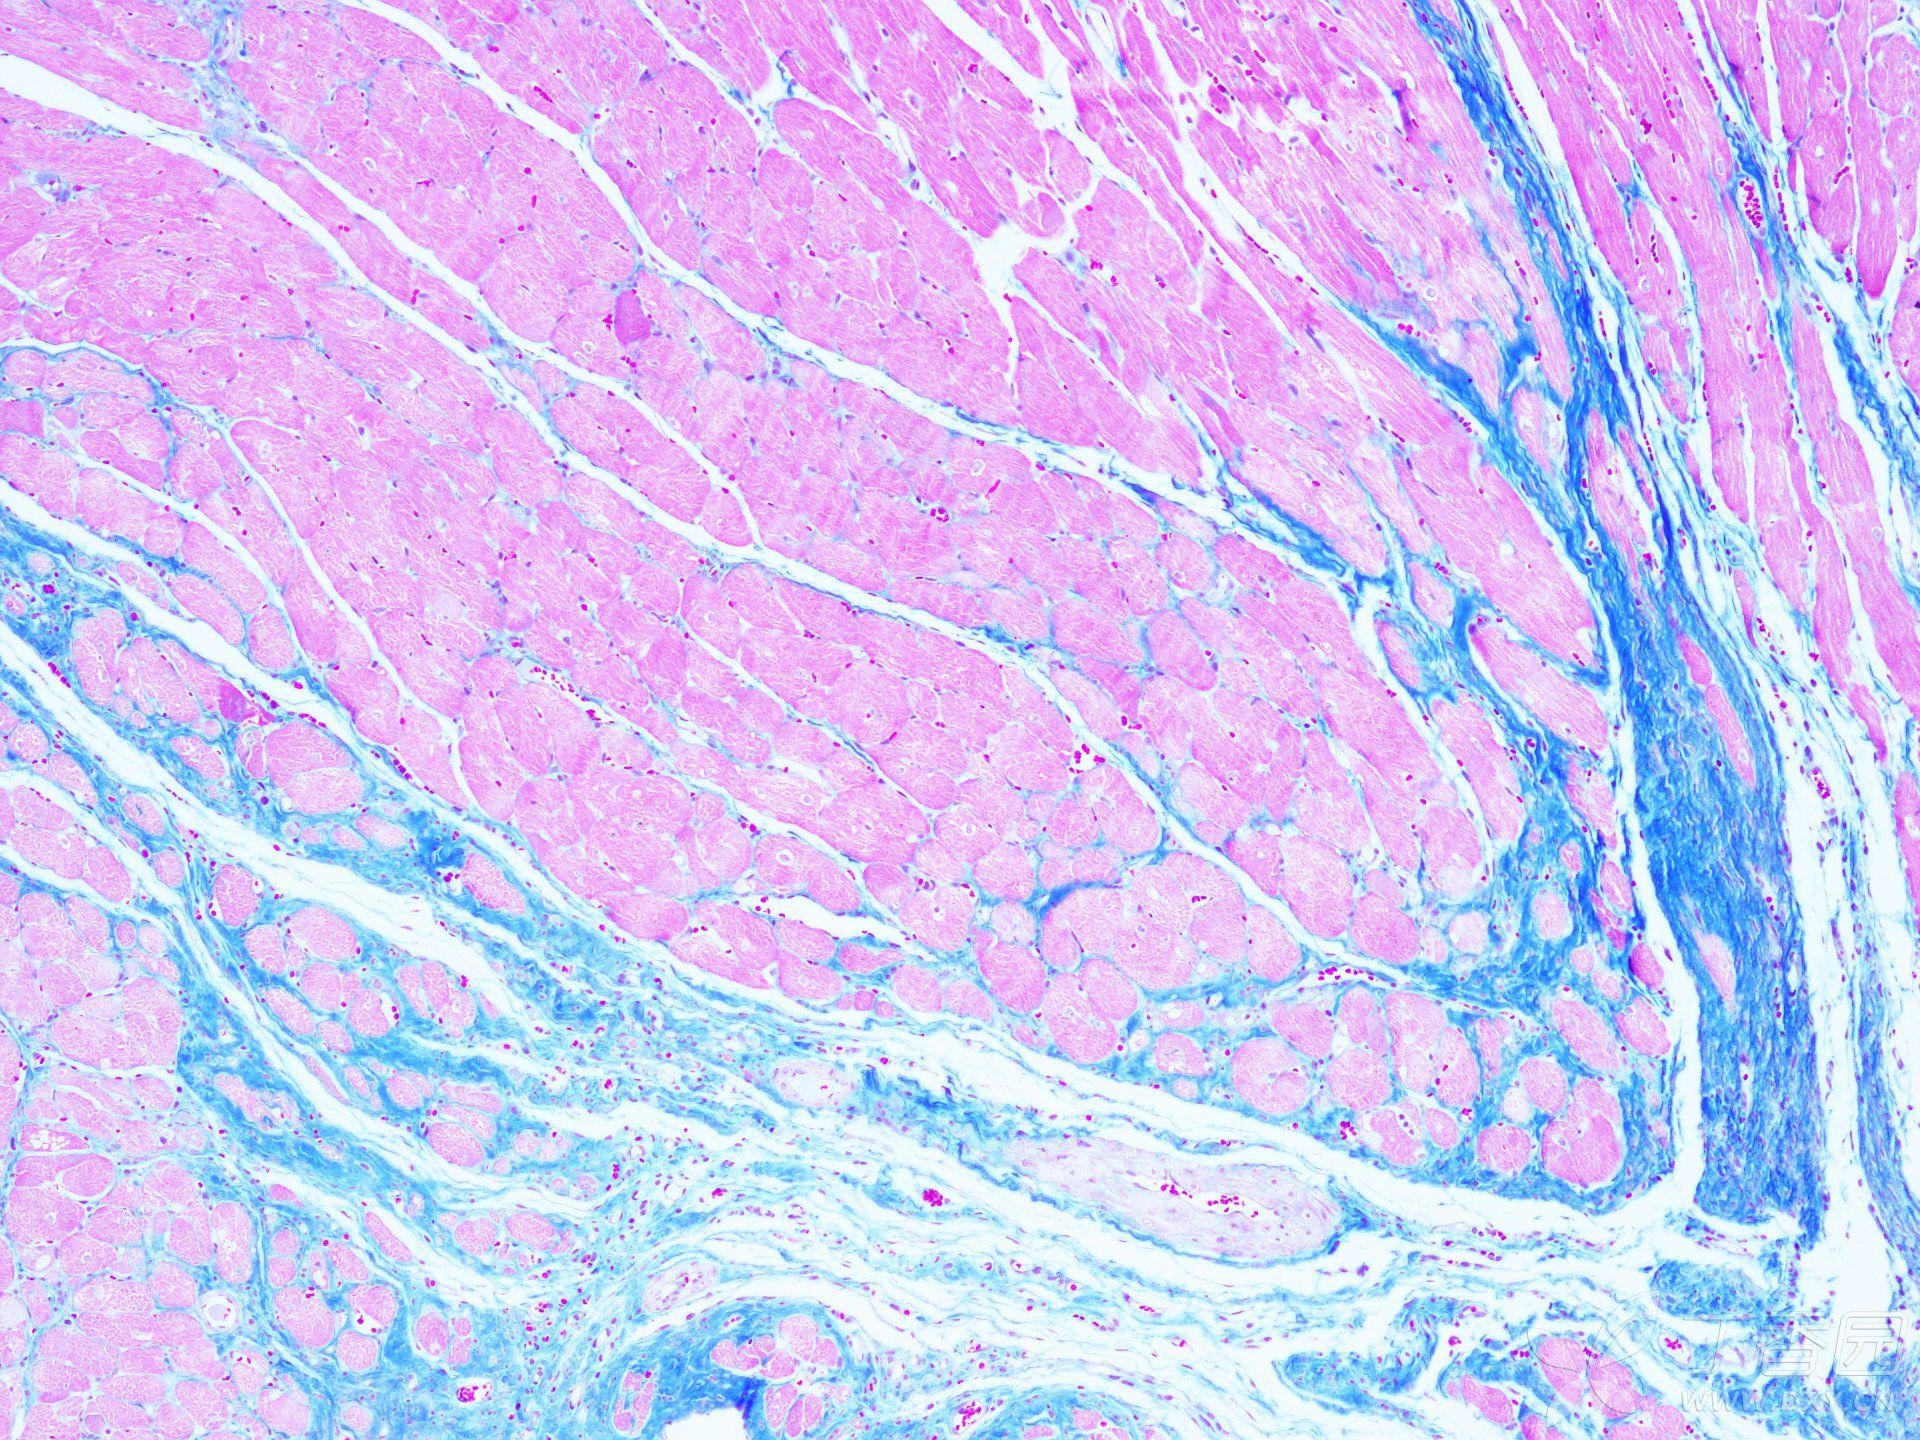

MASSON染色實(shí)驗(yàn)技術(shù)注意事項(xiàng)由普拉特澤生物為大家總結(jié)分享,普拉特澤生物病理染色實(shí)驗(yàn)平臺(tái)專業(yè)承接HE染色實(shí)驗(yàn)外包、油紅O染色等組織染色實(shí)驗(yàn)代做服務(wù),積累專業(yè)豐富的實(shí)驗(yàn)操作經(jīng)驗(yàn)。上次我們分享Masson染色實(shí)驗(yàn)報(bào)告分析不夠詳細(xì),有一些注意事項(xiàng)沒有寫出來,那今天咱們就為大家專門出一期詳細(xì)探討MASSON染色實(shí)驗(yàn)技術(shù)注意事項(xiàng),幫助大家更好的理解和應(yīng)用這個(gè)技術(shù),快點(diǎn)學(xué)起來吧!

MASSON染色作為一種重要的組織學(xué)染色方法,具有廣泛的應(yīng)用價(jià)值。然而,要想獲得準(zhǔn)確的染色結(jié)果,我們需要注意多方面的因素。從選擇合適的組織樣本、嚴(yán)格控制染色時(shí)間和溫度、注意染色劑的配制和保存,到細(xì)心觀察和處理染色結(jié)果,每一個(gè)環(huán)節(jié)都至關(guān)重要。